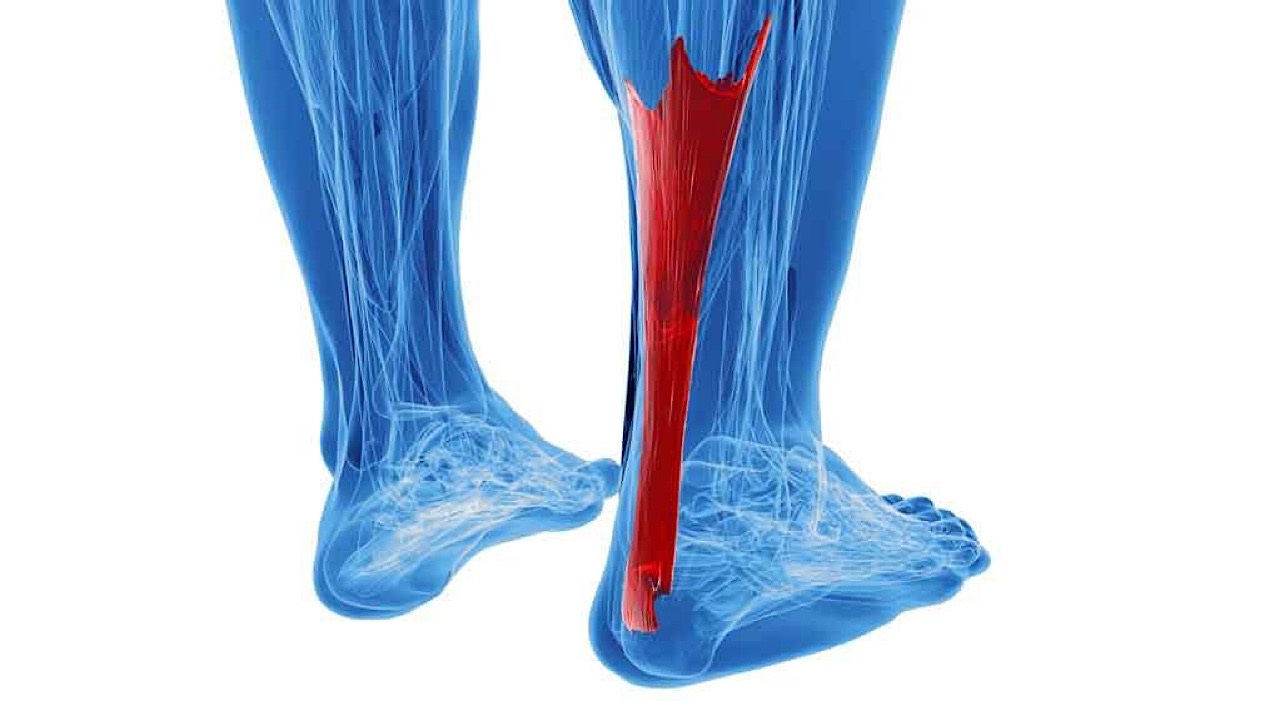

علماء يبتكرون طريقة جديدة لعلاج تمزق وتر العرقوب

منذ 2 سنة

0

2137